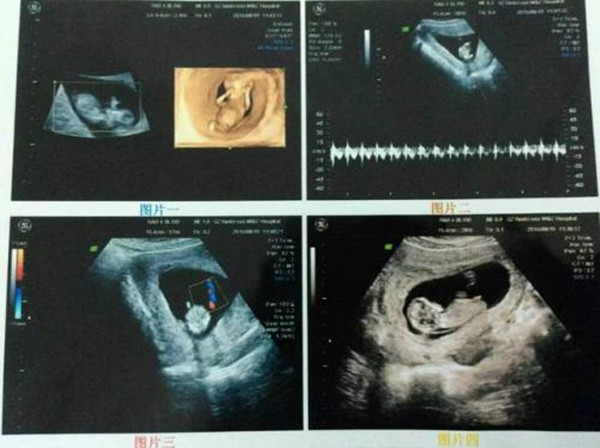

第二点:看nt图像 , 男孩女孩nt图差别很大

男孩和女孩的nt图像差别很大 , 男宝宝 , 彩超图可看到亮点 , 有突出的小JJ的标志;女宝宝 , 彩超图可看到三条白线 , 有小凹槽 , 那是女宝的小阴唇 。